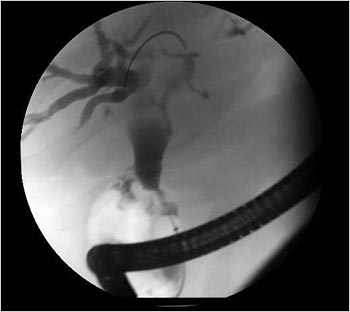

内視鏡的逆行性胆管膵管造影(ERCP: Endoscopic Retrograde Cholangiopancreatography イーアールシーピー)は、通常は病院の内視鏡検査設備の中、もしくは外科手術センターで行われます。超音波内視鏡と呼ばれる特別に細く軽いチューブが口から入り、下がって胃、小腸の最初の部分(十二指腸乳頭部)に到達するまで挿入されます。

その内視鏡を通ってカテーテルと呼ばれる小さなチューブが胆管、膵管の中に挿入されます。造影剤はこの管を通って挿入され、X線写真が撮影されます。これらの画像は、腫瘍や他の要因で、管が狭まったり詰まったりしていないかを示してくれます。また、がんの疑いのある病変について、内視鏡から主膵管に挿入されるカテーテルを通して、膵液が採取され細胞診が行われることもあります。

ERCP Image 1Image courtesy of Shawn Mallery, MD & Minnesota Pancreas and Liver Center